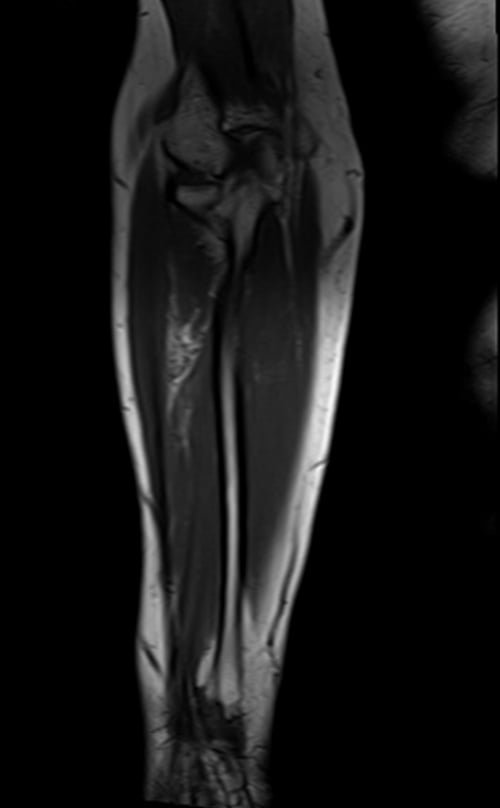

mri fore arm coronal t1 image 1 - MRI